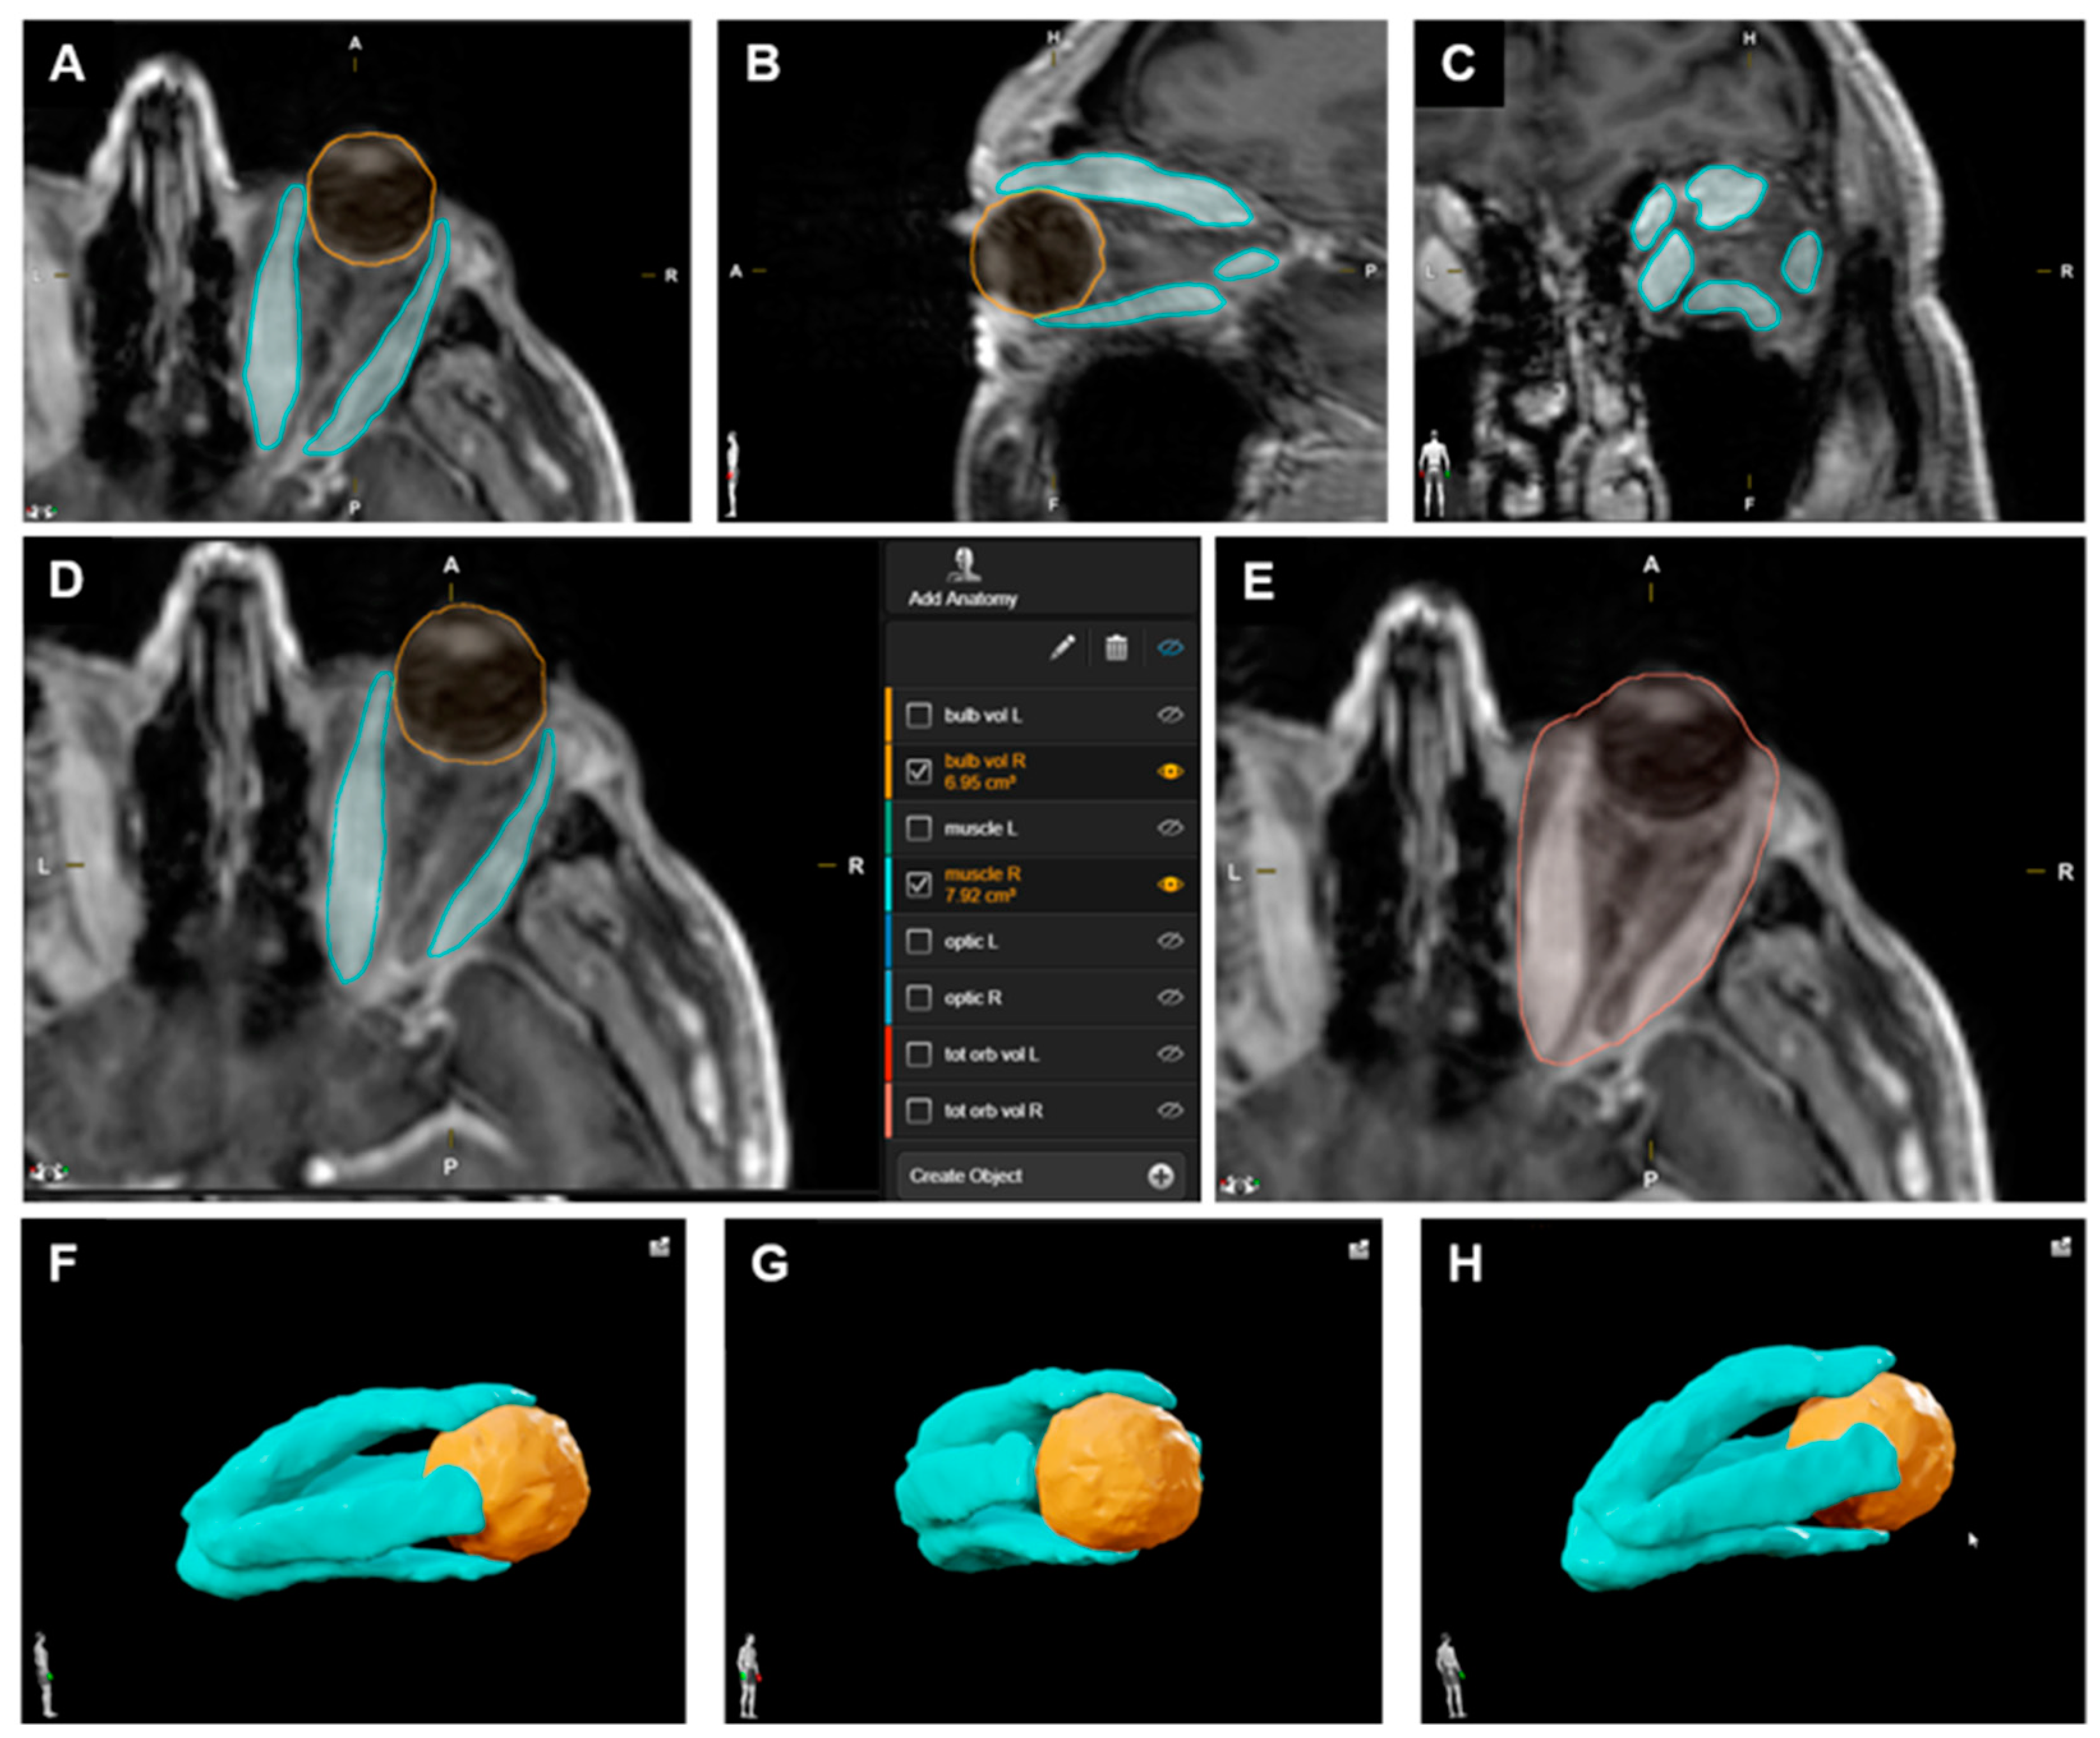

2.2. Volumetric Analysis